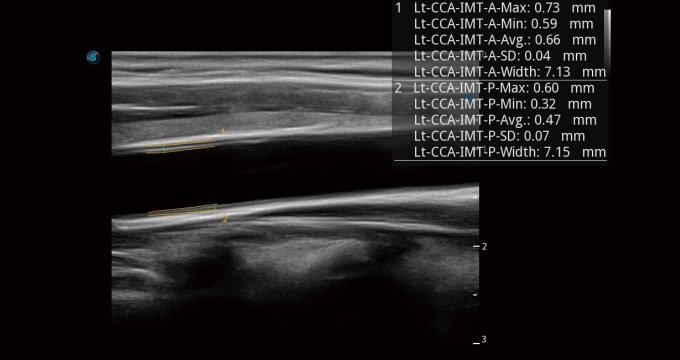

Auto-IMT

Auto IMT ist ein intelligentes Instrument zur Analyse des potenziellen Risikos eines Patienten für Herz-Kreislauf-Erkrankungen. Durch Anklicken einer Schaltfläche können Sie sowohl die Intima-Media-Dicke sowohl der Vorder- als auch Hinterwand der A.carotis communis messen. Dieses einfache Verfahren steigert die Produktivität der Untersuchung und erhöht ihre diagnostische Aussagekraft.